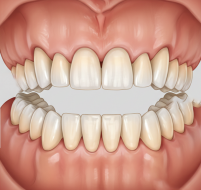

Правильный прикус — это не только ровная улыбка и эстетика лица. От того, как смыкаются зубы, зависит работа височно-нижнечелюстных суставов, жевательных мышц, состояние зубов и даже осанка. В этой статье разберём, что считается правильным прикусом, как его определить и почему важно следить за его формированием с раннего возраста.

Прикус — это соотношение зубов верхней и нижней челюсти при их смыкании. Он формируется постепенно, начиная с раннего детства, и зависит от наследственности, роста челюстей, наличия или отсутствия вредных привычек и своевременного прорезывания зубов.

С точки зрения ортодонтии правильным считается ортогнатический прикус, при котором:

Такой прикус обеспечивает равномерное распределение жевательной нагрузки.